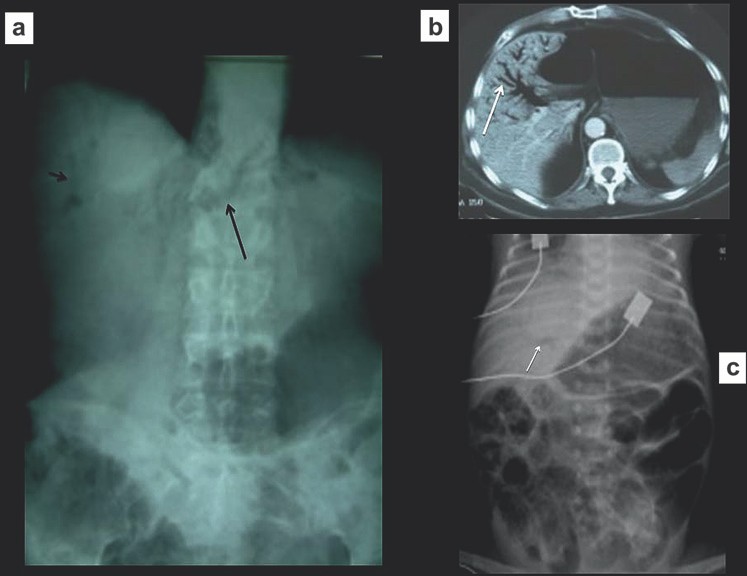

Dạ dày giãn to là dấu hiệu đặc trưng của tắc đường xuống của dạ dày và có thể phát hiện một cách dễ dàng trên các phim X quang (Hình 7). Tắc đường xuống của dạ dày có nguyên nhân phổ biến nhất là loét dạ dày-tá tràng. Các nguyên nhân khác bao gồm bệnh ác tính (liên quan tụy hoặc dạ dày), polyp, các tổn thương bẩm sinh, xoắn hoặc nang giả tụy. Dạ dày giãn mà không thấy cấu trúc nào bất thường cũng có thể xảy ra trong bệnh lý thần kinh do bệnh đái tháo đường.

Hình 7. Dạ dày giãn to (a) Phim X quang bụng thấy dạ dày giãn to, đầy khí (b, c) Chụp CT xác định dạ dày giãn to do tắc đường ra (xuống ruột). Lưu ý có ống thông mũi-dạ dày.